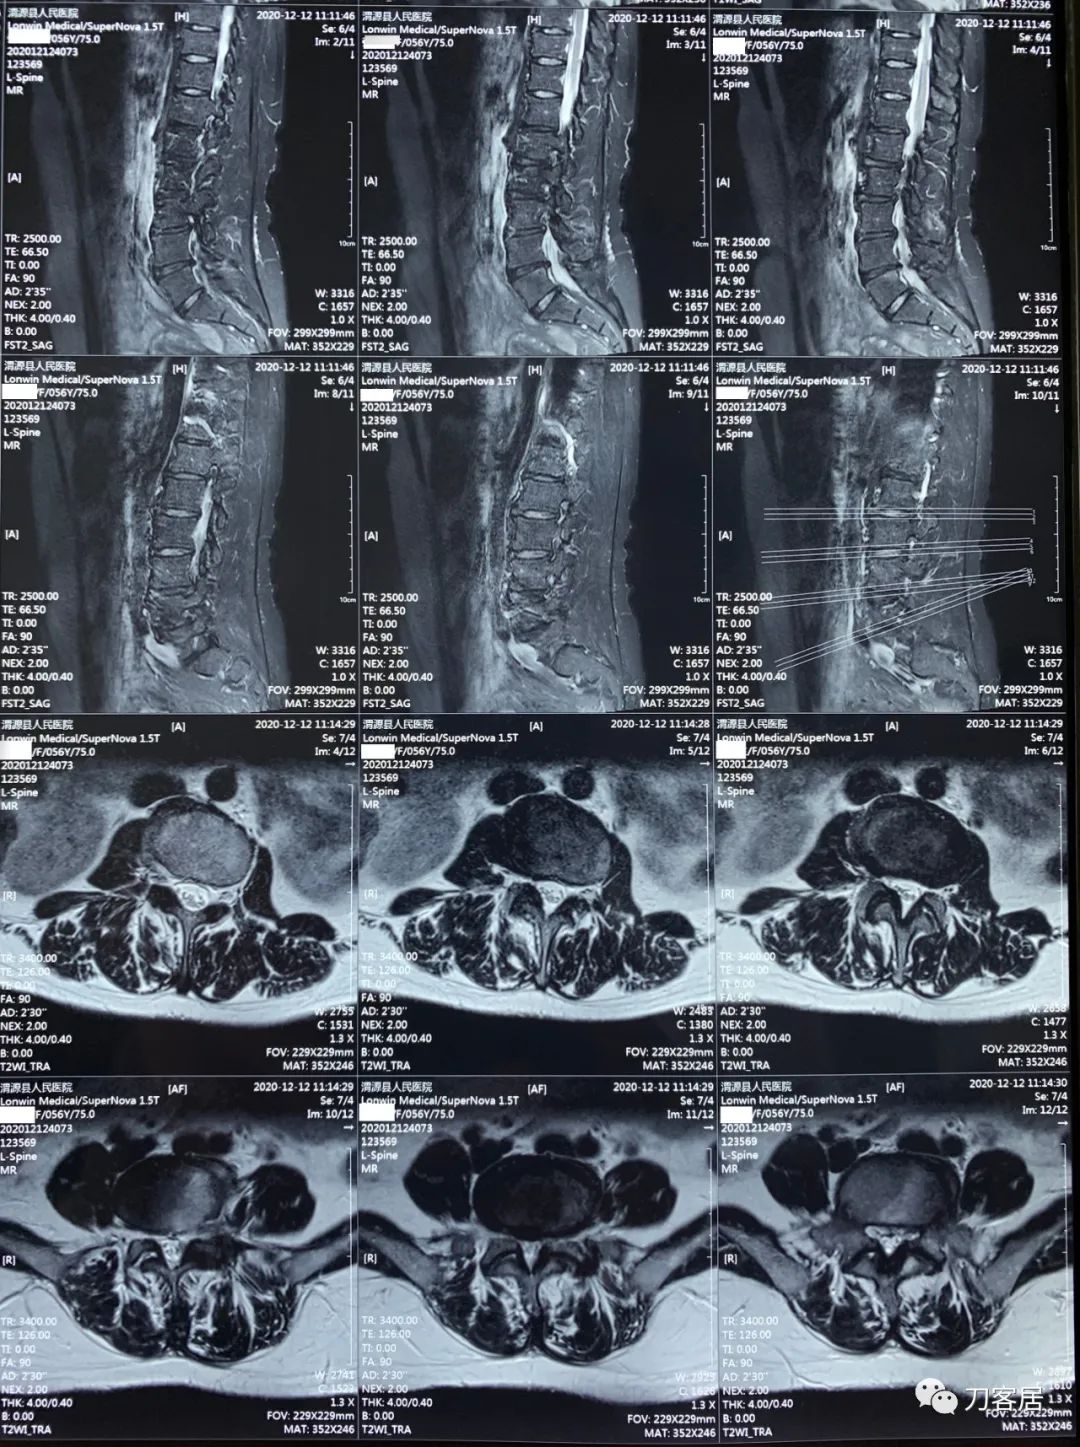

2021年12月12日去渭源县医院做颈椎腰椎MRI,提示1.腰椎侧弯畸形并骨质增生,2. L5S1椎体终板炎(I型), 3. L1-S1椎间盘变性并腰2-4,腰5骶1椎间盘膨出,腰4-5椎间盘突出并相应平面继发性椎管狭窄。2020年12月中旬于渭源县医院行骶管注射2次6针后睡眠改善,

2021年5月17日,西京医院骨科门诊找我就诊,自带影像学检查资料提示腰椎侧弯,腰3-4,腰4-5椎间盘突出,黄韧带肥厚,椎管狭窄。

从这个患者的影像资料分析,颈椎间盘突出问题不大,没有明确的上位神经元损伤表现,所以,不考虑颈椎和胸椎问题。腰椎侧弯畸形,但不严重。因为存在腰椎侧弯,使得腰椎MRI在扫描切面的时候,显示的椎间盘突出或椎管狭窄会有一定的误差,所以,又加做了经椎间盘的CT平扫,影像表现并不严重,综上,腰椎间盘突出,腰椎管狭窄,腰椎侧弯,不考虑手术治疗。同时,患者的主要痛苦是心理疾病,而不是器质性疾病,所以,以心身疾病治疗为主。虽然患者骨密度检查结果提示正常,但X线片显示骨质疏松,且其症状也与骨质疏松的症状有符合之处,比如静息痛,不能入睡,动作及姿势变换时痛加重等,所以,给予实验性抗骨质疏松治疗,以观疗效。